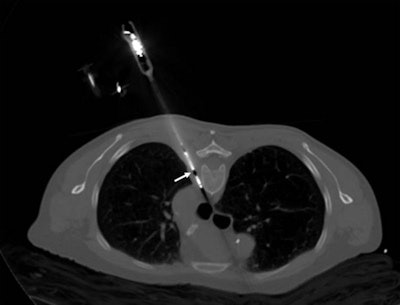

Tumor patients are a sensitive and highly specific group. The pain is usually very severe, cannot be controlled by analgesics, and is inaccessible to other procedures, so this is where interventional radiology comes in. With painful osteolytic processes, such as, for instance, bone metastases, we can carry out cementation and stabilization using minimally invasive access or we can destroy the tumor locally with CT-guided probes inserted into a painful area of tumor, and this is called ablation.

The most common procedure is thermal ablation, which "cooks" the tumor tissue. Thermal ablation can be used even with large tumors because it treats only that part of the tumor which is causing the pain. The effect is the patient is no longer aware of the pain, even if the thermal ablation cannot destroy the entire tumor.